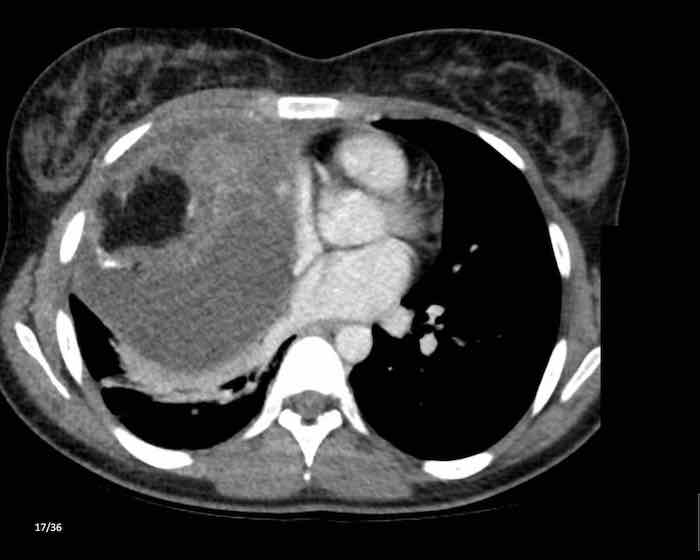

Các hình ảnh này của một phụ nữ 65 tuổi có tiền sử mắc bệnh Graves, một rối loạn tự miễn liên quan đến tình trạng cường chức năng tuyến giáp.

CT được thực hiện vì lý do ho ra máu.

Hình ảnh

Có một tuyến ức to lớn, cồng kềnh chứa mô mỡ đại thể.

Đây là hình ảnh điển hình của tăng sản tuyến ức.

Tăng sản tuyến ức trong bệnh Graves có liên quan đến tình trạng dư thừa hormone tuyến giáp và kháng thể kháng thụ thể thyrotropin.

Tình trạng này thường cải thiện sau khi điều trị thành công bệnh Graves.